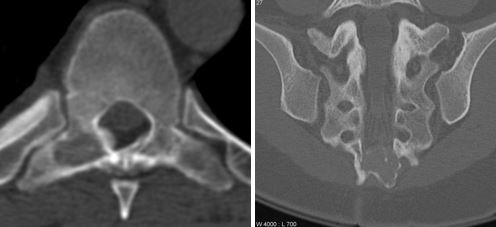

Твердые, костистые отростки в пояснично-крестцовой области часто свидетельствуют о следующих патологиях:

- осложнения остеохондроза – выпадение межпозвоночных дисков, которое прощупывается под кожей;

- нестабильность и смещение тел позвонков;

- деформирующий остеоартроз;

- спондилез, характеризующийся появлением наростов и отложением солей по краям позвонков.

Дегенеративные процессы в позвоночнике

Для справки! При остеохондрозе и его осложнениях наросты на позвоночнике чаще всего образуются на поздних стадиях, и сопровождаются другими симптомами – ограничение подвижности, нарушение чувствительности, болевые ощущения в пояснично-крестцовом отделе, слабость мышц.